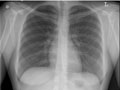

days. Chest X-ray| Normal: | The lungs look normal in size

and shape, and the lung tissue looks normal. No growths or other masses can be

seen within the lungs. The

pleural spaces (the spaces surrounding the lungs) also look normal. |

The heart looks normal in

size, shape, and the heart tissue looks normal. The blood vessels leading to

and from the heart also are normal in size, shape, and appearance. | The bones including the spine

and ribs look normal. | The

diaphragm looks normal in shape and

location. | No abnormal collection of

fluid or air is seen, and no foreign objects are seen. | All tubes, catheters, or other